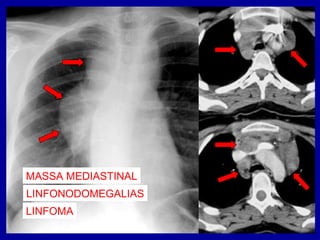

LESÃO EXPANSIVA MEDIASTINAL

MASSA MEDIASTINAL

ALTERAÇÕES DOS CONTORNOS

DESVIO DA TRAQUEIA

LINFONODOMEGALIAS

LINFOMA